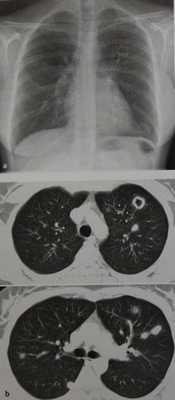

(Слева) На рентгенограмме органов грудной клетки в прямой проекции у пациента с гранулематозом с полиангиитом в обоих легких визуализируется очаги и объемные образования, некоторые с признаками кавитации.

(Справа) На аксиальной КТ без КУ у этого же пациента в легких визуализируются множественные очаги и объемные образования с признаками кавитации, сопоставимыми с некрозом. Сочетание полостных очагов, объемных образований, и участков консолидации - наиболее типичная лучевая картина гранулематоза с полиангиитом. (Слева) На аксиальной КТ без КУ у этого же пациента, выполненной несколько недель спустя, определяется разрешение патоло гических изменений. Визуализируется резидуальный тонкостенный полостной очаг на фоне очагового фиброза и рубцов в левом легком. Патологические очаги в легких обычно прогрессивно разрешаются. Во многих случаях остаются резидуальные изменения или рубец.

Гранулематоз Вегенера у женщины 30 лет. На обзорной рентгенограмме и КТ грудной клетки видно несколько округлых очагов различных размеров с признаками расплавления в некоторых из них. В окружающей ткани реактивные изменения отсутствуют.

Гранулематоз Вегенера у мужчины 52 лет. Опухолевидная консолидация в верхней доле правого легкого. Аналогичные, но менее обширные инфильтраты имеются в другом легком.